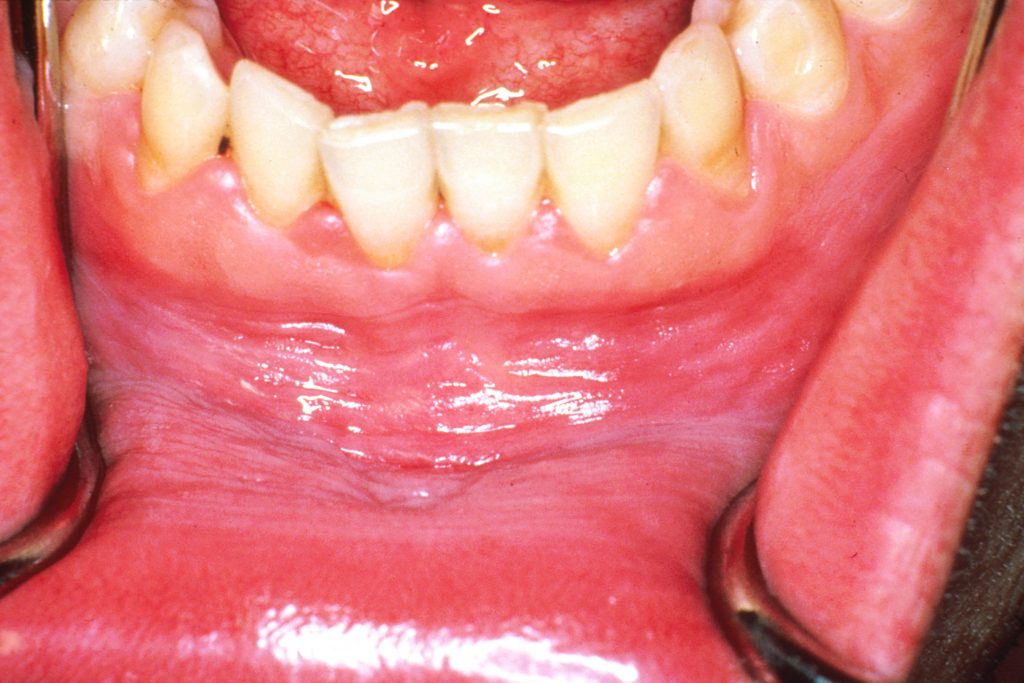

How Do You Get Rid Of A Gum Boil Fast . Fortunately, this article discusses the signs and. Web  thorough removal of plaque through using electric toothbrushes, oral irrigation devices or flossing aids can reduce the levels of plaque biofilm in. You’ll need treatment to stop the infection from spreading and to relieve symptoms. Web  a gum boil is an abscess that forms on the gum. It can be a gum boil. The abscess can form almost anywhere on the gums but is often seen between the gum and teeth. Web  do you see a bump on your gums? Web  how to get rid of a gum boil? Web  learn about the red, swollen bumps on your gums, also known as gum boils. Web  contact a dentist if you develop a gum boil. The symptoms include pain, swelling, the sensation of loose teeth, and bad breath. Treatment includes clearing out the abscess and starting antibiotics. You need to seek the help of a dentist for the treatment of a gum boil. When an infection occurs below the.

You need to seek the help of a dentist for the treatment of a gum boil. The symptoms include pain, swelling, the sensation of loose teeth, and bad breath. Web  contact a dentist if you develop a gum boil. Web  learn about the red, swollen bumps on your gums, also known as gum boils. It can be a gum boil. Treatment includes clearing out the abscess and starting antibiotics. You’ll need treatment to stop the infection from spreading and to relieve symptoms. Web  do you see a bump on your gums? Web  how to get rid of a gum boil? Web  a gum boil is an abscess that forms on the gum.

How Do You Get Rid Of A Gum Boil Fast  Web  thorough removal of plaque through using electric toothbrushes, oral irrigation devices or flossing aids can reduce the levels of plaque biofilm in. Treatment includes clearing out the abscess and starting antibiotics. Web  a gum boil is an abscess that forms on the gum. It can be a gum boil. Web  thorough removal of plaque through using electric toothbrushes, oral irrigation devices or flossing aids can reduce the levels of plaque biofilm in. Web  contact a dentist if you develop a gum boil. The abscess can form almost anywhere on the gums but is often seen between the gum and teeth. You’ll need treatment to stop the infection from spreading and to relieve symptoms. When an infection occurs below the. Web  how to get rid of a gum boil? Web  learn about the red, swollen bumps on your gums, also known as gum boils. The symptoms include pain, swelling, the sensation of loose teeth, and bad breath. You need to seek the help of a dentist for the treatment of a gum boil. Fortunately, this article discusses the signs and. Web  do you see a bump on your gums?